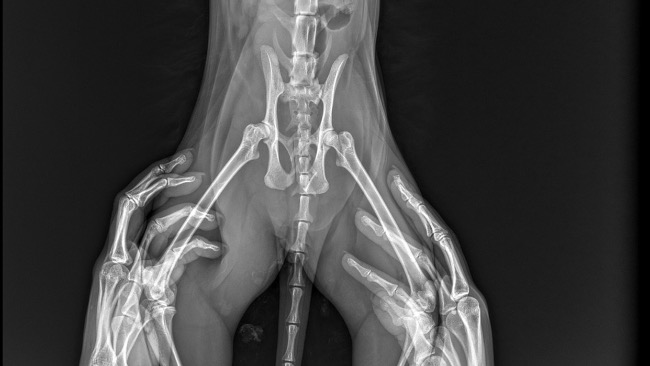

lista problemów:

-stłuczenie płuc

-złamany kieł szczęki - 103

-wyrwany pazur IV KMP

-złamany paliczek KMP

-złamanie miednicy

-krwiokocz